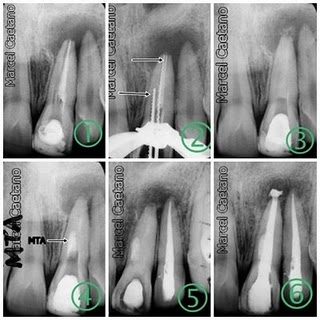

Caso Clinico

Paciente apresentou-se com lesão periapical veja RX inicial, foi indicada a cirurgia e no ato foi retirado material para exame histopatologico, para se descobrir a natureza da lesão.

Notar que a raiz do dente vizinho esta inclinada pela presença da lesão, suspeita de Cisto.O Cisto aumenta de tamanho sempre causando grande perda óssea, causando se não tratado deformidade óssea e dental podendo ser fatal.

Antes da Cirurgia